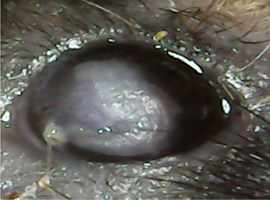

この「CP4715」をAKC様の病態を発症したFADSマウスに点眼投与すると(2回/日、14日間)、眼病変が著明に改善することを、今回見出しました。「CP4715」を投与した場合、眼の炎症が改善し、眼の血管新生も改善しました。

| コントロールマウス(FADSマウス) | FADSマウス(CP4715投与) | ||

| CP4715を投与すると炎症が改善する | |||